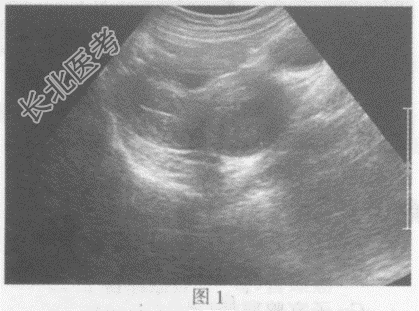

- 单项选择题临床资料:女性患者, 32岁,自述不规则阴道出血半月余。超声综合描述: (图1经腹扫查;图2、彩图经阴道扫查)子宫颈形态失常, 宫颈后唇可见低回声区,边界尚清晰, 形态规则,向外突起, CDFI:其内可见丰富动静脉血流信号。